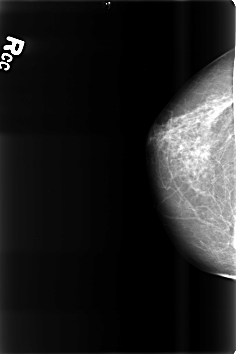

B_3471_1.RIGHT_CC

RIGHT_CC LINES 4600 PIXELS_PER_LINE 3064 BITS_PER_PIXEL 12 RESOLUTION 50 NON_OVERLAY